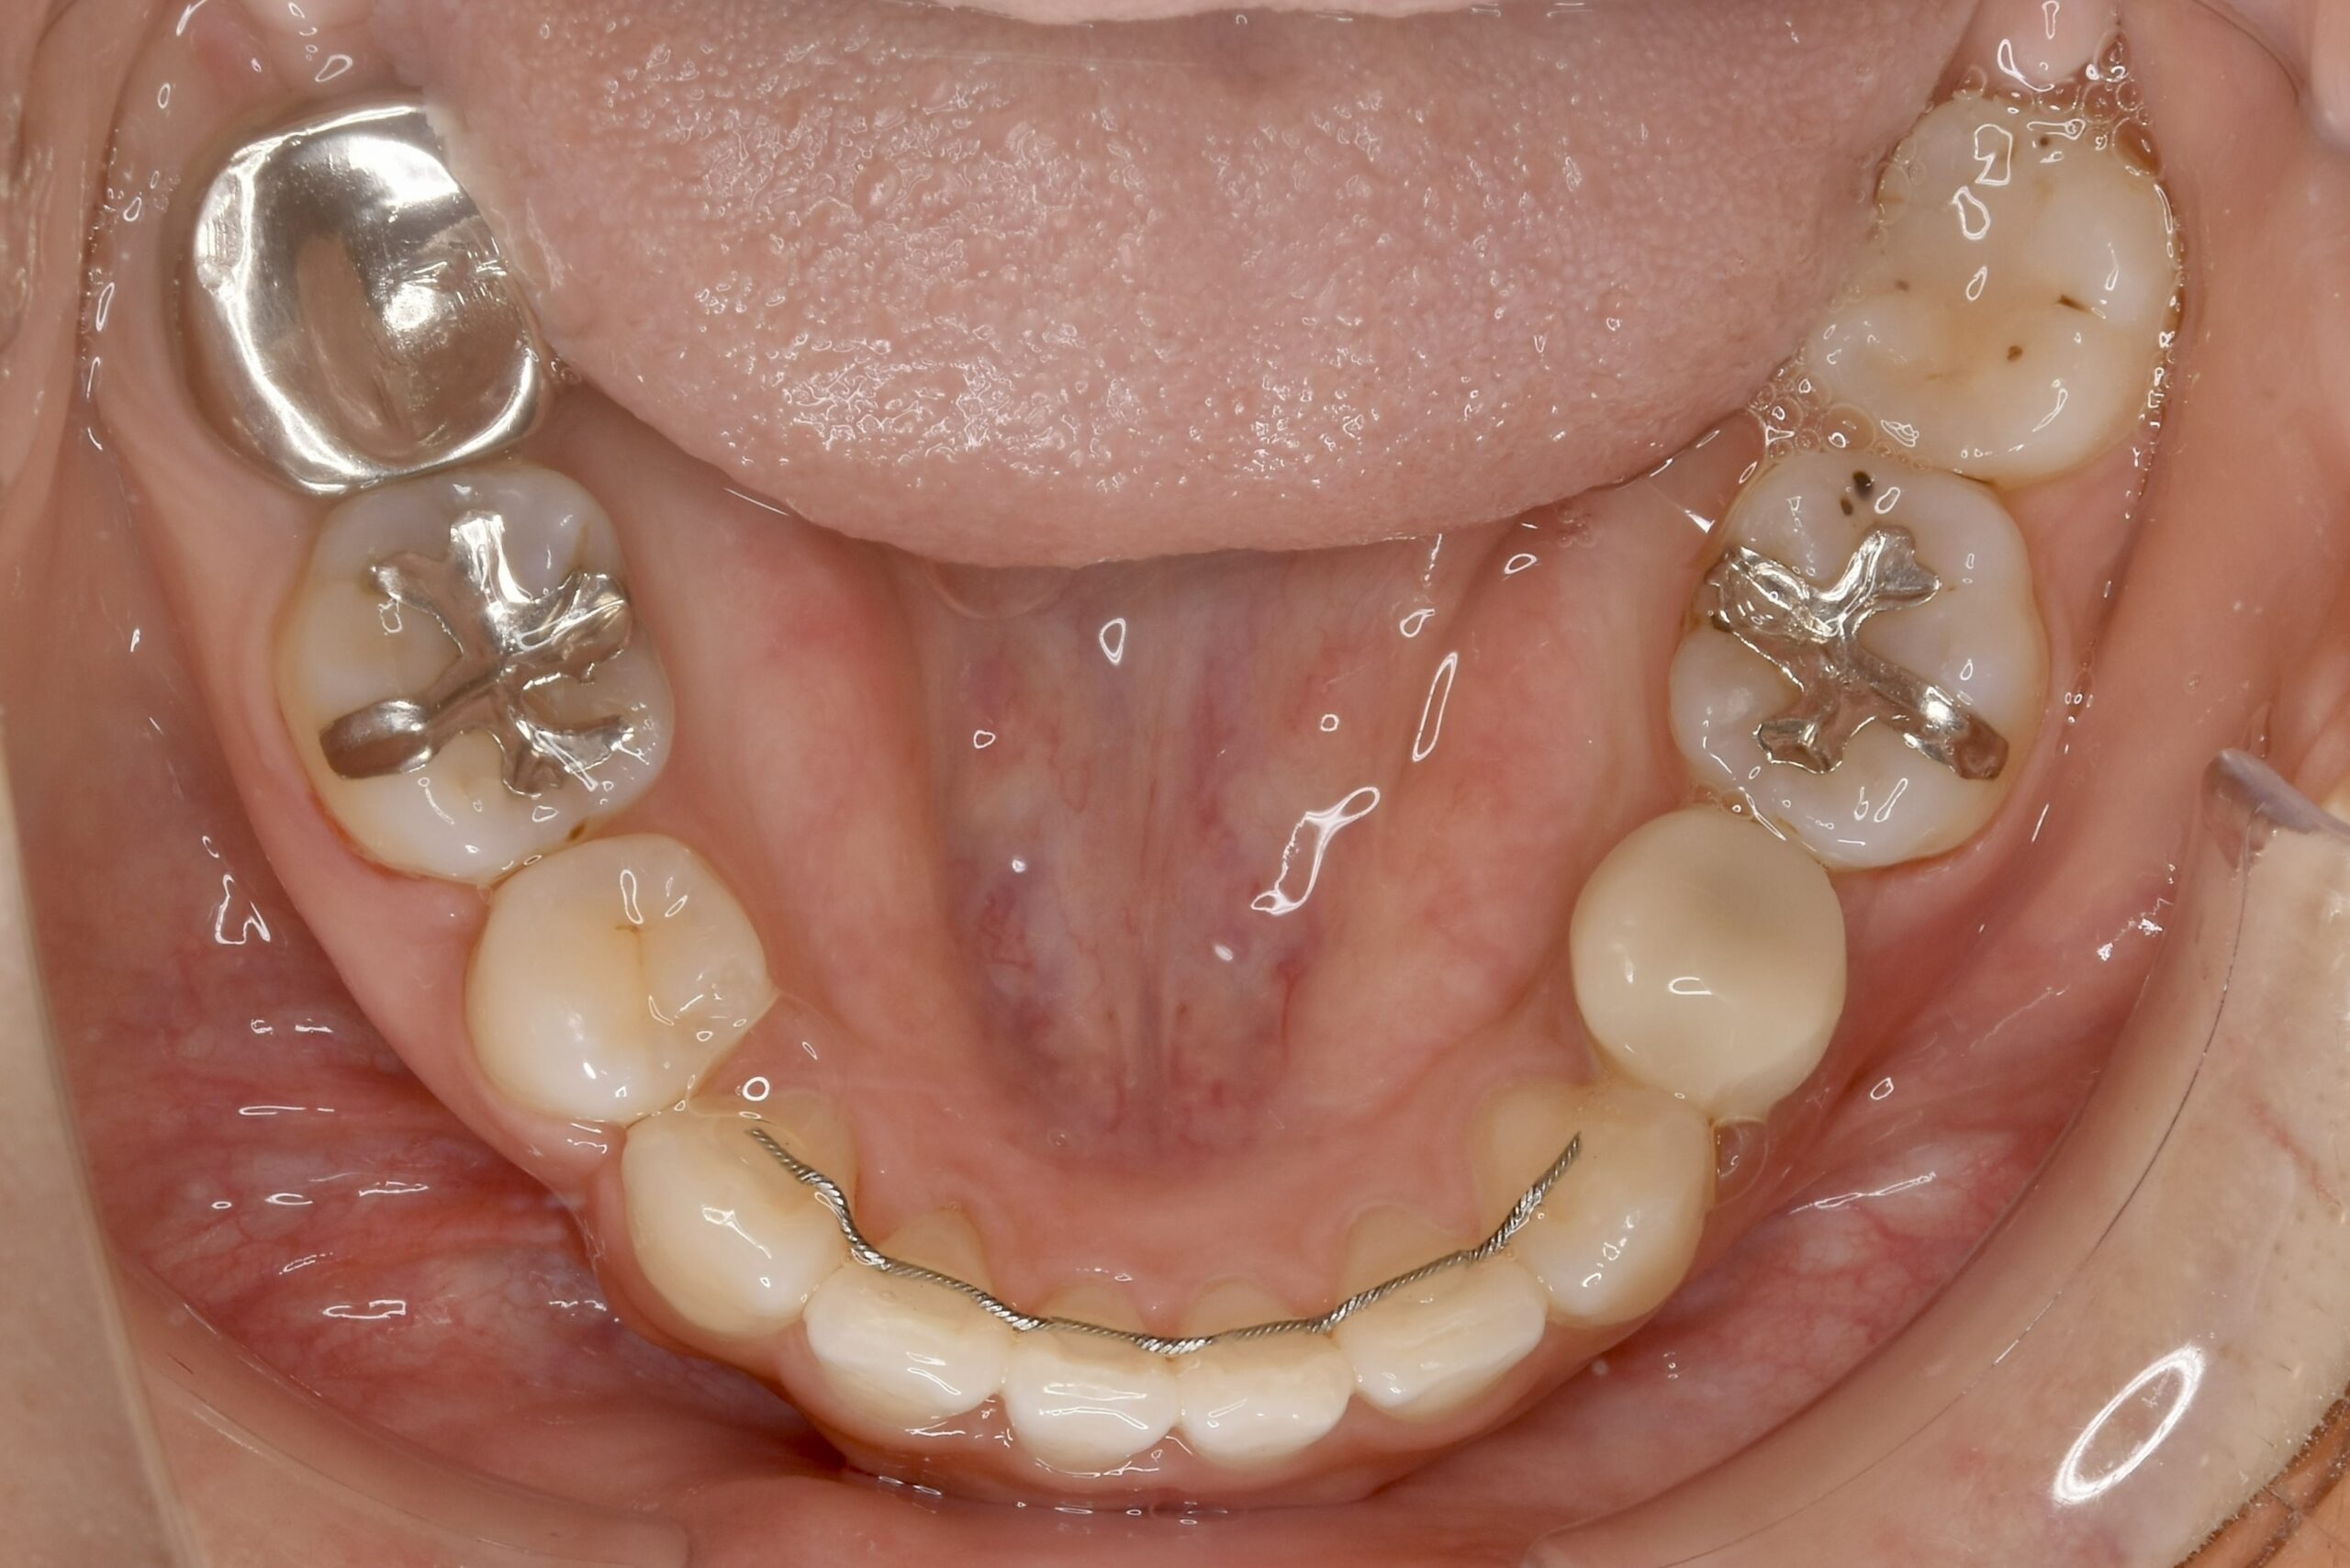

32歳 女性 治療期間:1年7ヶ月

BEFORE

診断名・主な症状 叢生を伴う上顎前突

治療内容 上下とも歯を2本抜いて、上の前歯を後方に引きながら、でこぼこを治しました。

抜歯部位 上 両側4番目

下 右側4番目、左側5番目